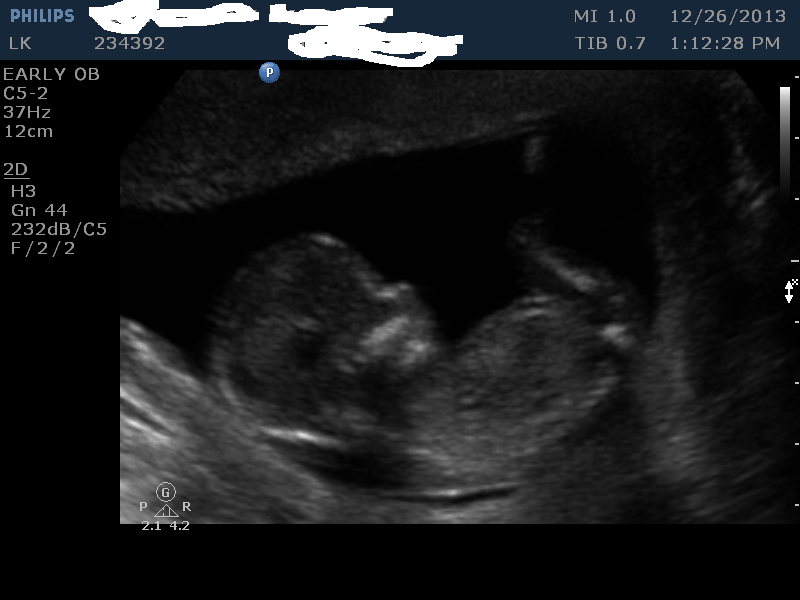

I had my 13 week scan done today. This is baby number 5, I currently have 4 girls and 1 boy. We would be happy either way. I just find it fun guessing. I do not think any of the pics have a good nub, but maybe I am wrong.

Nub guess?

skull guess?

placenta guess? (not sure it is even in photo)

Attachment 15893